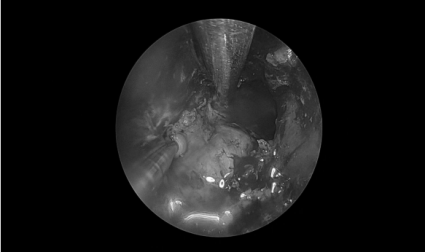

耳内镜检查:分泌性中耳炎(右)

电子喉镜检查:鼻息肉(双)

双耳鼓膜完整,右侧鼓膜内陷明显,右侧鼓室可见积液